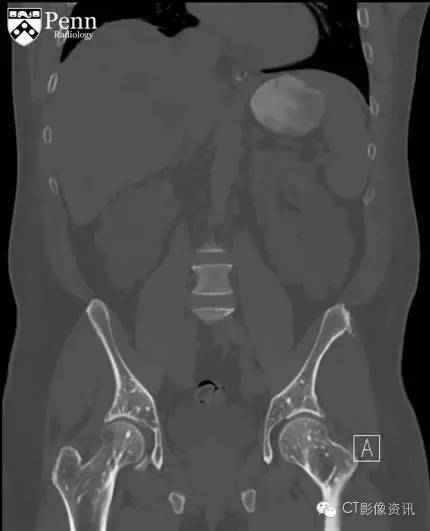

腹盆部冠状位以及轴位CT影像骨窗显示多个边界清晰的细小硬化灶呈现圆形、卵圆形以及线样;其直径从几毫米到一厘米不等,分布在股骨以及髋臼顶部;不伴有骨膜反应和骨质破坏。在软组织窗冠状位CT图像显示双侧肾影增大,伴随大量囊样密度影;此外在肝脏也可见囊样密度;可能为常染色体显性遗传多囊肾后遗症导致。

最终诊断:骨斑点症